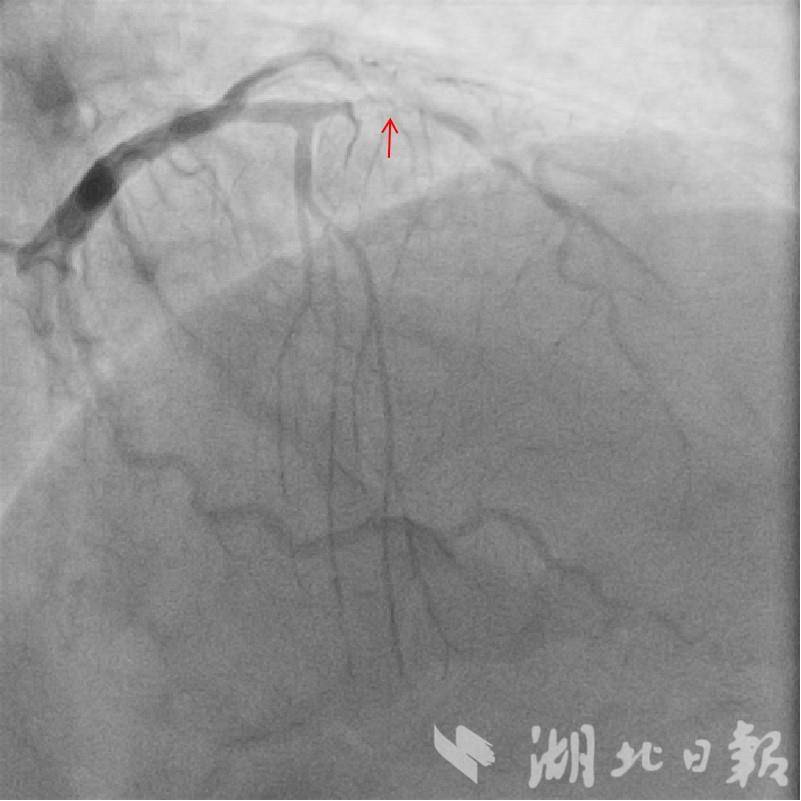

10月 27日,在麻醉科的配合下,手术正式开展。王朗团队仅靠X 线指引,将导引导管、导引钢丝精准送入病变血管,通过预扩张球囊打开闭塞部位后,送入IVUS 导管。借助这一“血管内超声探头”,团队精确测量病变参数、确定支架规格及定位点,再以分支血管导丝为标记,成功完成支架置入。术后IVUS 复查显示,支架位置精准、膨胀充分、贴壁完美,手术圆满成功,夏先生转危为安。